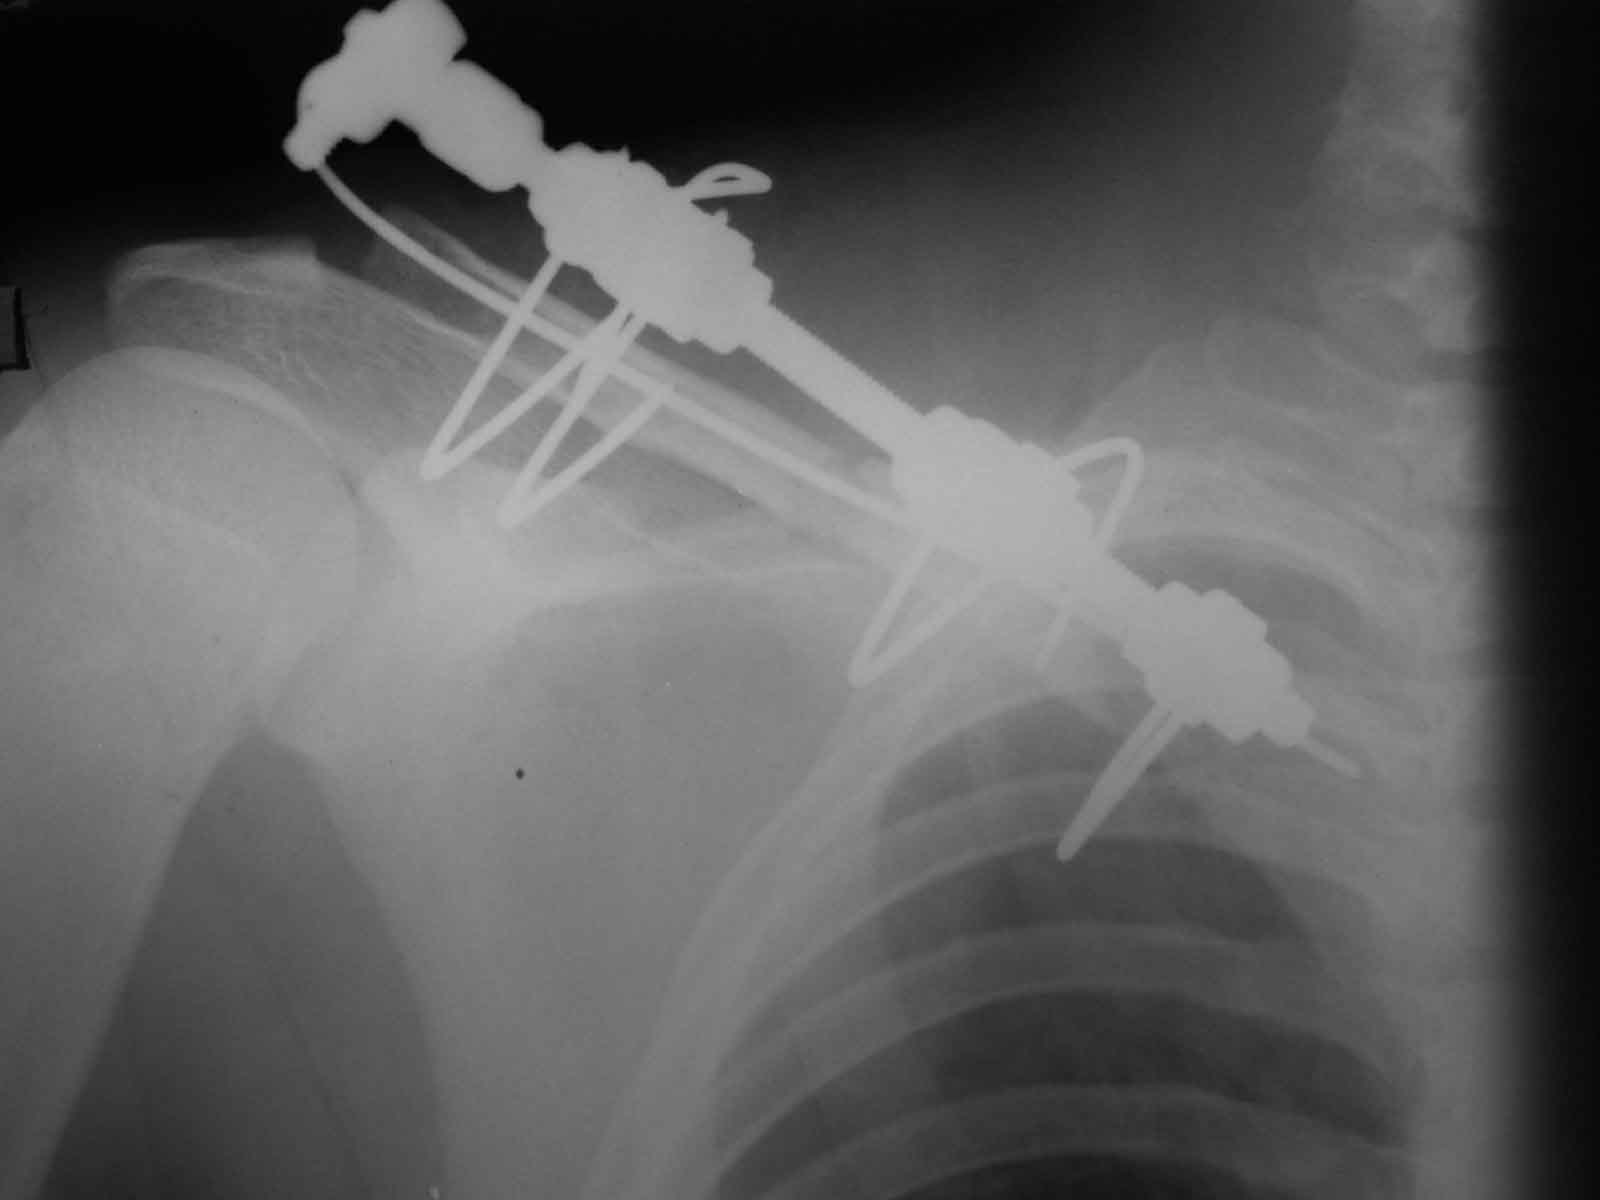

Виктор, если я не ошибаюсь, мы по Новосибу знакомы. Закрыто делаю так: после укладки на валик под лопатки со свешивающимся со стола локтем (руку можно под поясницу, а лучше на веревочку и кисть на живот. Порпобовать как отломки репонируются руками (обычно плохо), потом каждый отломок аккуратно цапкой захватываю и еще раз пробую репонировать. Это помогает выявить направление в котором репозиция дистигается легче всего и исключить наличие "мышечного перемота". Центральный отломок цапкой поднимаю и под кожей определяю его торец. Спицу в канал и рукой до упора, делее дрелью до выхода из кожи, потом дрель на другую сторону и спицу поглужаю под обрез отломка. Репозиция цапками за оба отломка. Пальцами определяется сопоставление, а ассистент пробивает спицу по каналу в переферический. После пробивания 2 - 3 см. уже теряется подвижность и это является контролем точности проведения. Далее как пожелаете. Понятно, что мы фиксируем наружной конструкцикй из 2 - 3 консольных спиц поперек в каждфй отломок, фиксированных на обычном резьбовом стержне на толстых шайбах.Доп.иммобилизация не нужна.

Один из вариантов, что удалось быстро найти, позже еще найду, но схема примерно такая (первое

вложение).

Мужик кочегар, срок нетрудоспособности 7 недель. Наружную конструкцию сняли через 3 недели. Далее без иммобилизации. Погруженную спицу можно убрать и через несколько месяцев, если жить не мешает.

Раньше не погружали, на рентгенограммах и натуре видно (последние 2 вложения). Как вариант спицы в периферическом отломке могут крепится на трехдырочную приставку, что дает возможность компрессии.